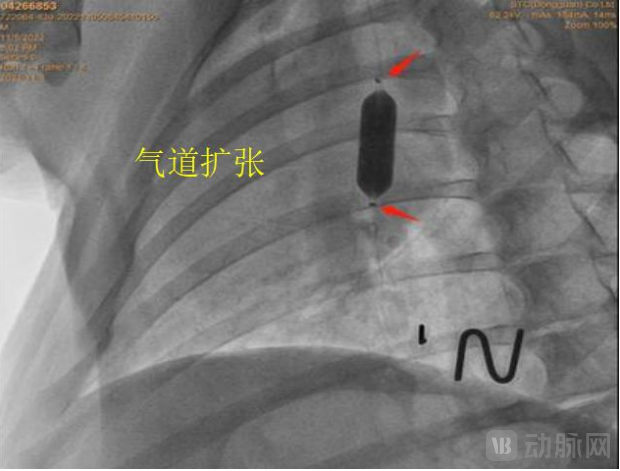

据介绍,呼吸道急救多功能球囊扩张导管拥有多通道及多级扩张球囊。多通道使得扩张、吸痰、给氧、活检等临床急救措施可在第一时间内同步进行。多级扩张球囊则涵盖8-20mm不同规格,满足几乎所有呼吸道的扩张需求。

第一,呼吸道急救多功能球囊扩张导管可保持患者呼吸道的畅通。将压力泵与三级扩张球囊通道连接,可对狭窄的呼吸道进行扩张疏通。其中,球囊位于导管远端,由特殊材料制成,在三个不同扩张压力下,对应三个不同的扩张直径,既节省医生的时间也节省病人的费用。球囊直径从6.0mm-20mm,长度覆盖30mm-55mm,可清理扩张呼吸道任何地方的狭窄或痰液堵塞。